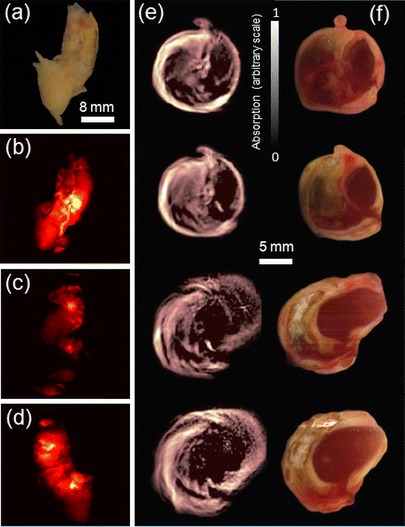

Imaging of Plaque Morphology and Planar Fluorescence

Figure 3b–d presents rotational images taken from a representative intact plaque sample (shown in Fig. 3a), from different view angles. Normally, MMP (fluorescence) activity should be mostly concentrated around the carotid artery bifurcation area, where most of the vulnerability is expected [18]. However, common plaques represent geometrically complex and highly heterogeneous structures, having multiple openings and large variations in vessel wall thickness and optical properties of different components. The multiple projection images and the rotational movie (available as Supplementary Information online) evince that the excitation and emission light have been guided and attenuated non-uniformly in various areas of the plaque. This readily leads to erroneous conclusions regarding the origin of the fluorescent signals that are being detected by the CCD camera located outside the sample and in any case does not allow for a three-dimensional understanding of the disease extent. As an example, some of the light in Fig. 3d, that is thought as coming from the opening of the external carotid (branch) artery, could in fact originate from another location deep inside the plaque and guided through scattering-free areas. In another projection, shown in Fig. 3c, the bifurcation area does not show high levels of fluorescence. The likely explanation for this observation is that the branch artery is located relatively far away from the surface that is facing the CCD camera resulting in high attenuation of the light as it travels through a highly scattering and absorbing plaque area. The inaccuracy of planar fluorescence imaging has been previously discussed [19].

Fig. 3.

Rotational planar fluorescence imaging of an intact specimen and plaque morphology. a Color image of a human carotid specimen. b–d Fluorescence images from the same specimen embedded in clear agar phantom rotated with 90° steps. See also Video online of continuously rotated specimen. e Three-dimensional stack (2-mm vertical steps) of morphological optoacoustic images made from an intact specimen using 635 nm illumination. f The corresponding color images from dissected plaque.

Figure 3e shows three-dimensional morphological optoacoustic images resulting from an intact plaque. These data are obtained at a single wavelength of 635 nm at which activated MMPSense has low excitation efficiency so that mostly morphological information but not MMP activity can be extracted from the images. The morphologic characteristics have in-plane resolution on the order of 200 μm, limited by the useful bandwidth of the ultrasonic detector. Images at four different levels around the bifurcation area, all separated by 2 mm, are shown, revealing good correspondence to the color photographs of a sliced plaque (Fig. 3f). The 50-μm cryosections were obtained approximately from the same area where optoacoustic images were produced.